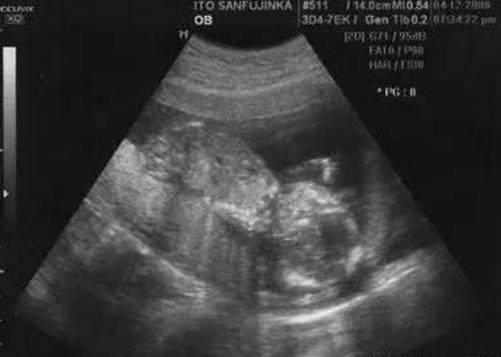

表姐在怀孕八个多月的时候,觉得肚子胎动比较迅速,总觉得有什么事情要发生,所以说就去医院检查,医生说胎儿脐带绕颈厉害,一旦有什么异常,就赶紧要来医院剖腹产,表姐回家之后把这件事情告诉了婆婆,婆婆劝说医生为了讹钱,什么话都说,根本就没问题。

就这样过去几天之后,表姐有一天晚上觉得肚子动的厉害,也就没有在意,可是之后两天却发现肚子里面没有胎动了,就赶紧去了医院,医生说宝宝已经胎死腹中,因为脐带绕胫而死亡的,了解这种情况之后,了解才发现,不是医生骗自己,而是自己有个婆婆太无知了。